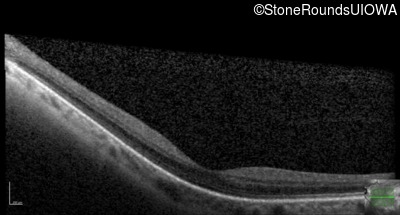

Age at visit: 41 years (Visit 2)

OD OS

This 41 year old woman was highly myopic as a child and experienced a rhegmatogenous retinal detachment OS at age 20.

Refraction OD:     -17.25 +1.00 x 93

Refraction OS:     -18.25 +3.50 x 56

The clinical features favoring the diagnosis of Sticker syndrome in this patient include extensive radial lattice degeneration, a personal and family history of rhegmatogenous retinal detachment, a history of cataract surgery before age 30 (and very high myopia before that), arthritis in her knees and hips and a slightly flattened mid-face.